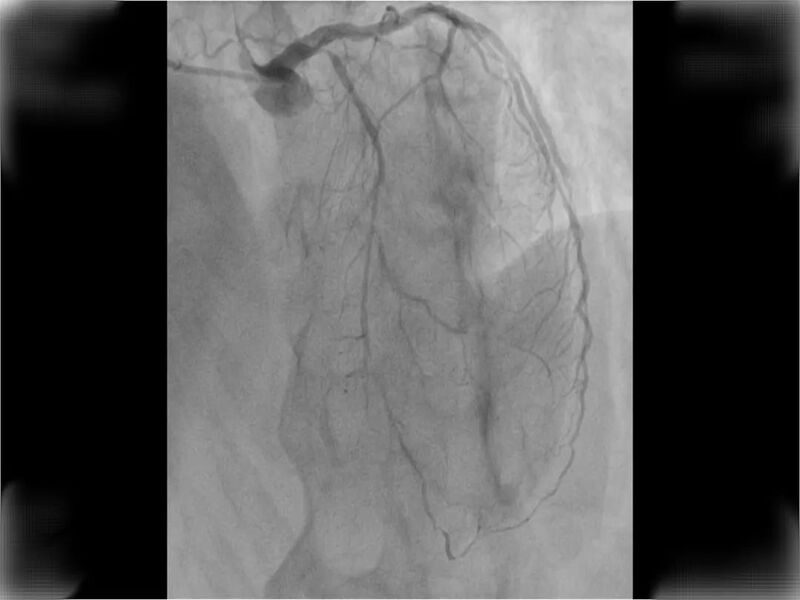

鉴于李先生仍有明显的闷胀性胸痛症状,吉心心内科团队立即启动急诊通道,将其直接送入导管室进行紧急手术。术中发现,患者左前降支血管狭窄程度高达99%,薛国宏医生迅速开通闭塞血管,并成功植入两枚支架。

术后患者病情逐渐稳定,心肌坏死症状得到明显改善。据李先生回忆,春季气温回暖让他放松了警惕,此前已经出现胸闷症状却并未引起足够重视。这次能够及时就医并得到有效的干预,实属幸运。